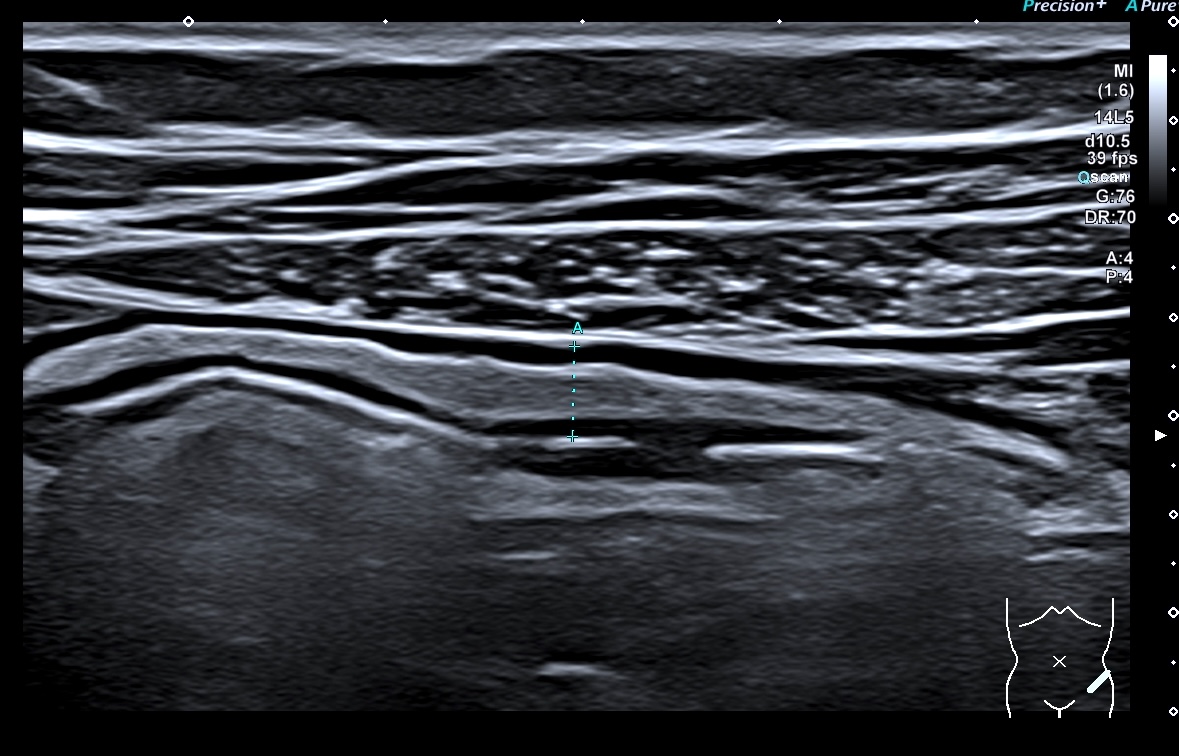

Paroi 4,1 mm et Doppler négatif (Limberg 0)

Score de Milan = 5,74 (1,4 x4,1 +0)

Donc la maladie va mieux, l'évolution est favorable

Mais la maladie reste active (non cicatrisée).